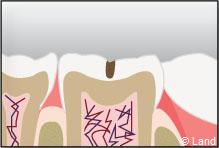

Un inlay reconstitue l’anatomie dentaire en comblant une cavité taillée dans la dent.